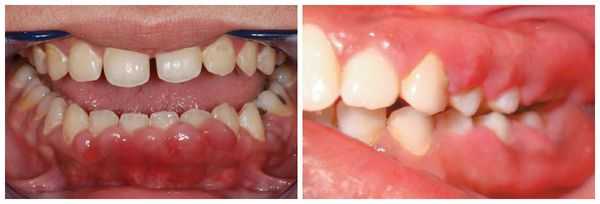

При осмотре стоматолог видит изменение цвета поражённых участков слизистой, гипертрофию (увеличение объёма) межзубных сосочков и края десны. Обычно в области воспаления присутствует зубной налёт, зубной камень и поражения кариесом. При обследовании стоматологическим инструментом десна может кровоточить. При хроническом воспалении клиническая картина стёрта, но может наблюдаться выраженная гипертрофия мягких тканей. При длительно текущем процессе разросшаяся десна может закрывать практически всю коронку зуба. При десквамативной ( с появлением пузырьков на дёснах) и язвенной форме гингивита на десне могут образовываться пузырьки и язвочки [3] .

- Гипертрофический гингивит. Сосочки между зубами увеличиваются, со временем они могут полностью закрывать коронки зубов. Десна приобретает синюшный оттенок, кровоточит во время еды, чистки зубов или при стоматологическом осмотре, формируются глубокие десневые карманы.